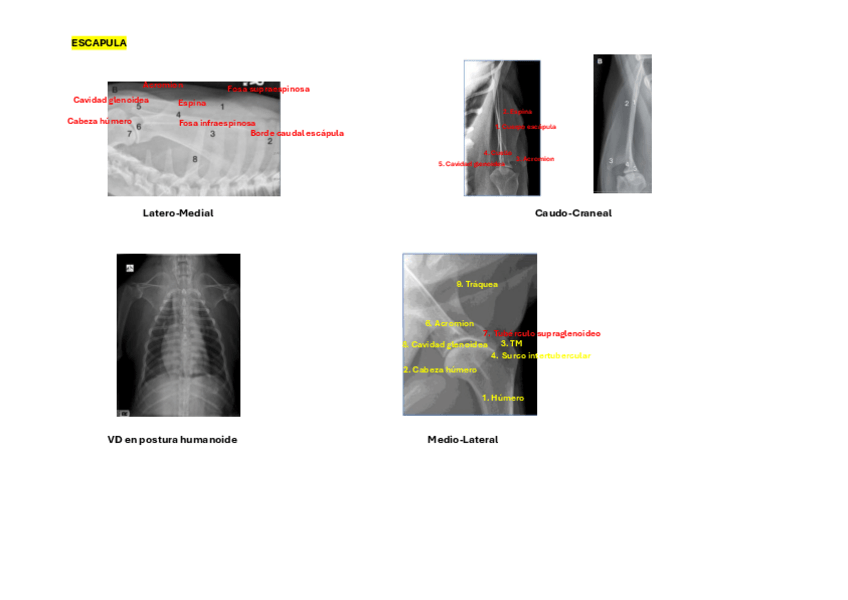

Imágenes de radiografias explicadas

He publicado nuevos apuntes de 3º Diagnóstico Por la Imagen: Imágenes de radiografias explicadas

Rx-miembro-anterior.pdf